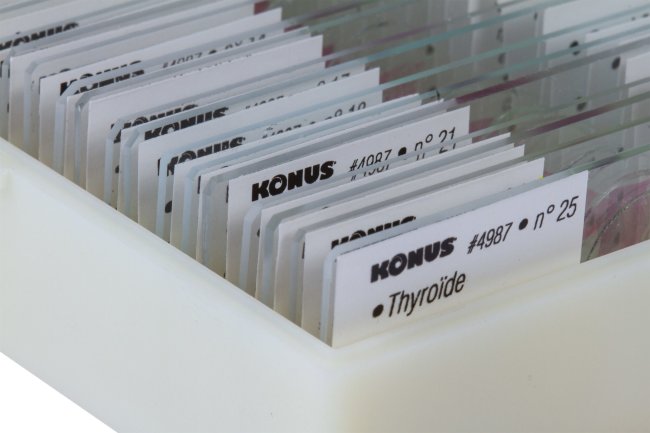

- Комплект из 25 специальным образом подготовленных образцов

- Каждый микропрепарат снабжен уникальным номером и имеет подпись на 8 языках

- Набор поставляется в удобной и прочной коробочке

25. Щитовидная железа.